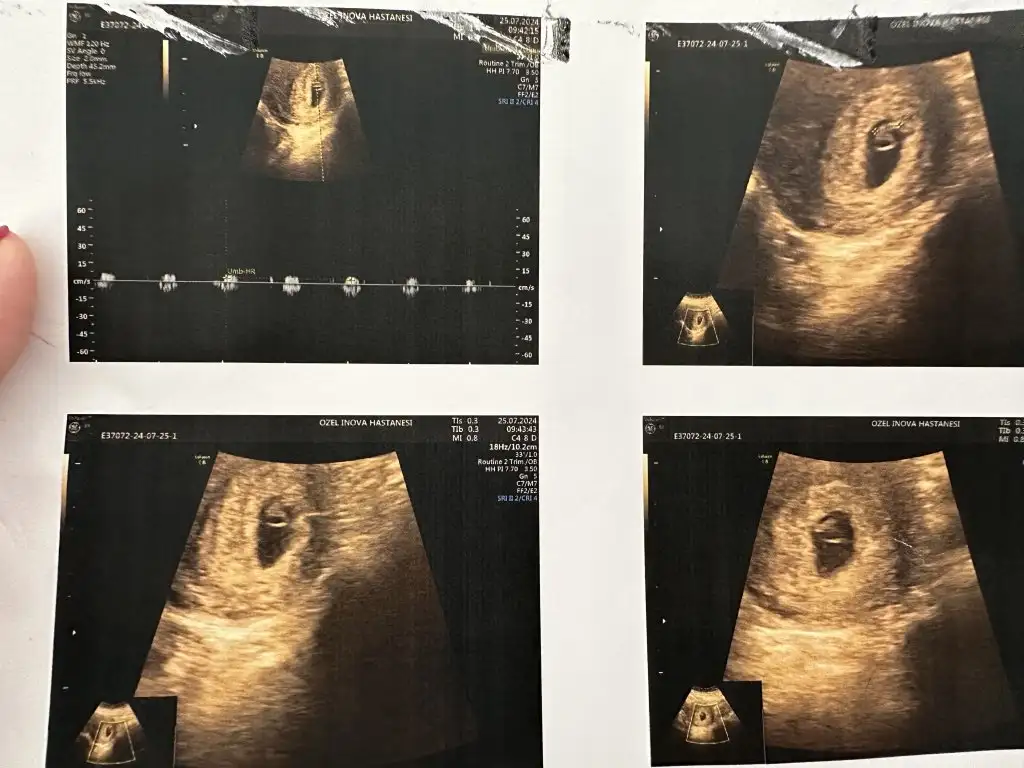

Mınnoslarım kalp atısını duyduk daha küçükmüş hemen kapadı 3 sanıye falan dınledık 120 ymiş atım hızı gayet ıyı dedı,kesenın ortasında buuu meloşuumm melegim can melegim can 🤭 yalnız bulantıdan bu hafta vıtamınlerımı bıle alamamıstım ıkı gun gerıye düşmüş yavrucagım kendıme dıkkat etmelıyım,kanama alanıda hıc kalmamıs🥰🥰🥰 fnd_50 fnd_50 melegim can melegim can Papatyamaviss Papatyamaviss destinesiaa destinesiaa melisaa93 melisaa93 golden-snitch golden-snitch A afravetafra Perlitik Perlitik T tweeetyyy ve dıger mınnoslarım